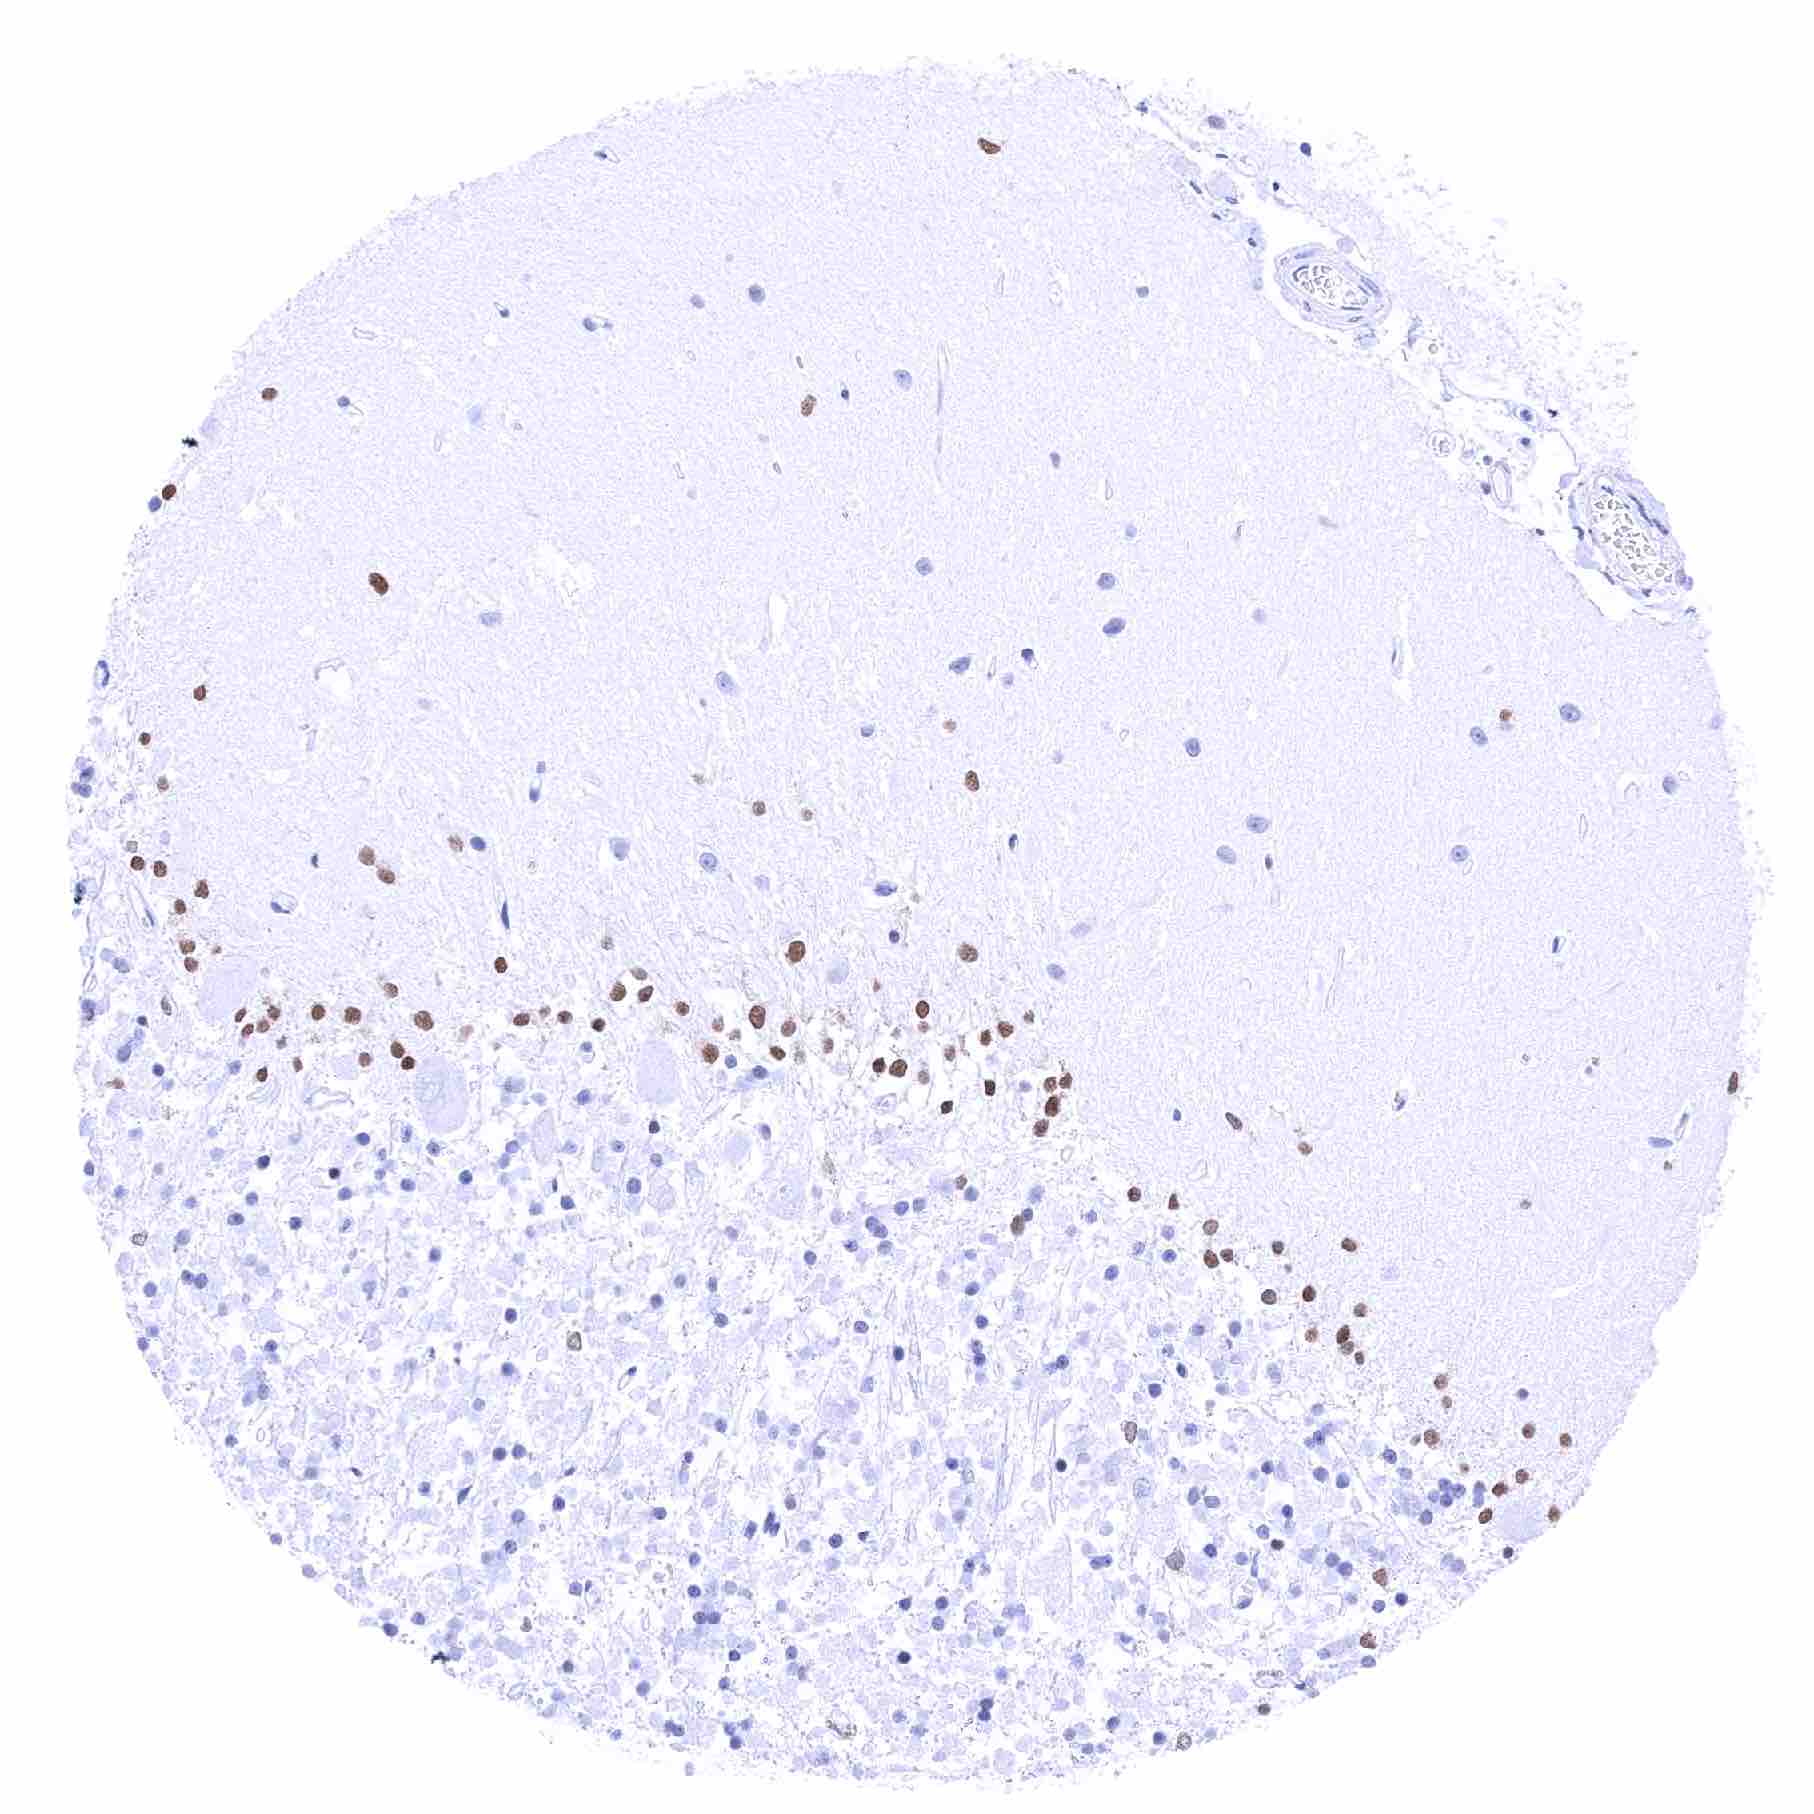

Cerebellum (molecular layer, Purkinje cell layer, granule cell layer)

Cerebrum, grey matter – Moderate to strong SOX2 positivity of a fraction of glial cells